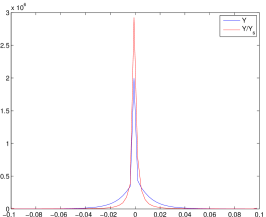

We observe that the weighted projection data admits a sparse representation than the measured projection data in wavelet frame domain. The distributions of wavelet frame coefficients (using piecewise linear tight wavelet frame system) are plotted in Figure 4. To have a fair comparison, and are normalized to the same scale, and the coefficients near the metal trace are removed. From the distributions we can see that the weighted projection data has a sparser representation than the original projection data . Therefore, the sparsity prior in the inpainting model (3.7) is more effective than directly using as input.

By combining (3.7) with (3.6), the proposed re-weighted JSR model is able to repair the degraded projection so that the repaired data is closer to , where is the Radon domain solution from (3.1) and is the unknown ground-truth CT image. Note that it is hard to obtain the ground truth image for polychromatic energy CT with varying attenuation coefficients with respect to the energy level, we choose the NCAT phantom (Figure 1(a)) as the approximated ground truth CT image . Empirically, the repaired projection data fits the linear inverse problem (1.2) better than the repaired projection data and computed from the NMAR and the unweighted JSR model (3.2) respectively. This is the key to the success of the re-weighted JSR model since the linear model (1.2) is what we commonly assume for CT imaging. Such linear assumption is not correct (though reasonable) for a multi-chromatic imaging system.

To support such claim, we present comparisons of with , , and in Figure 5 using the NCAT phantom. We observe that is a better approximation to the projection of the reference image than the repaired projection data from the JSR and NMAR model (see Figure 5(c),(d)). The NMAR model also generates a better repaired projection than the unweighted JSR model due to its re-weighting strategy. However, the unweighted JSR model is still able to reduce the majority of the metal artifacts in the reconstructed image due to its sparsity based joint regularization. These observations, together with the reconstruction results in Section 4, show that the re-weighted JSR model combines the merits of the NMAR model’s weighting strategy and the sparsity based joint regularization of the unweighted JSR model.

To quantitatively measure the difference between and the repaired projection data from different models and the measured projection data , we calculate the -norms , , and . Since the region of the metal trace has major contribution to these quantities, we also compute the -norms excluding the regions of the metal trace. Results are shown in Table 3. Obviously, the repaired projection data from the re-weighted JSR model is closer to than that from the NMAR and JSR model. However, although is closer to in regions outside of , is overall closer to than due to the inaccurate recovery of the projection data inside the metal trace by the re-weighted JSR model (see Figure 5(c)). This is probably why the re-weighted JSR model still cannot fully remove metal artifacts, though it improves over the unweighted JSR and the NMAR model.